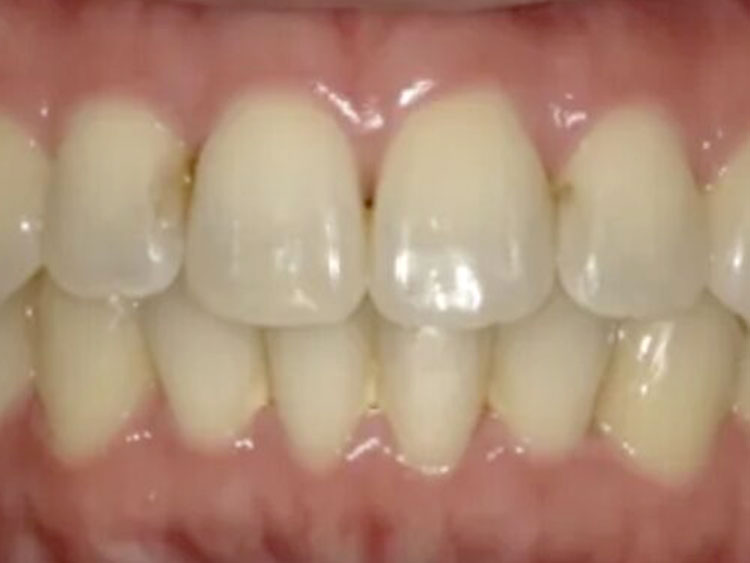

BEFORE

20代。 「前歯の傾きが気になる」「下の歯のガタつき」を主訴に来院。 検査の結果、上の前歯が下の前歯を深く覆ってしまう「過蓋咬合(Deep Bite)」の状態であり、見た目だけでなく噛み合わせの機能改善も必要でした。